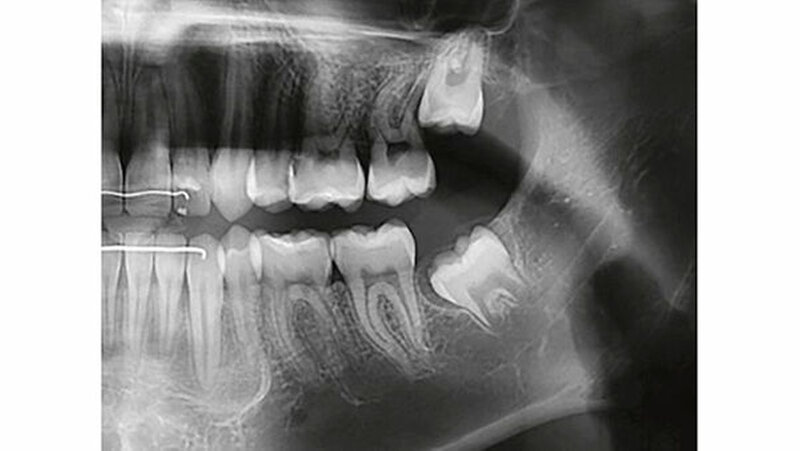

Auf dem mitgelieferten vier Jahre zuvor erstellten Orthopantomogramm (OPT) waren noch keine Hinweise auf das Vorhandensein einer Veränderung regio 32-34 sichtbar (Abbildung 2). Ein Jahr später konnte anhand des OPT bereits eine radioopake Struktur regio 33, 34 festgestellt werden (Abbildung 3). Auf dem aktuellen OPT und digitalen Volumentomogramm (DVT) zeigten sich regio 32-34 lingual multiple, rundliche, unterschiedlich große Radioopazitäten, umgeben von einer radioluzenten Zone.

Die Ränder der radioluzenten Zone waren sehr gut zum umgebenden Alveolarknochen abgrenzbar (Abbildung 4, 5). Eine dreidimensionale Diagnostik (DVT) macht aus dreierlei Gründen Sinn: 1. Erleichterung der Patientenaufklärung, 2. optimale Lagebestimmung des Tumors in Bezug zu benachbarten anatomischen Strukturen wie Nachbarzähne und Nerven, 3. präoperative Bestimmung der Anzahl zahnähnlicher Strukturen (zusammengesetztes Odontom), um kontrollieren zu können, ob während des operativen Eingriffs alle hartgewebigen Tumoranteile entfernt worden sind.